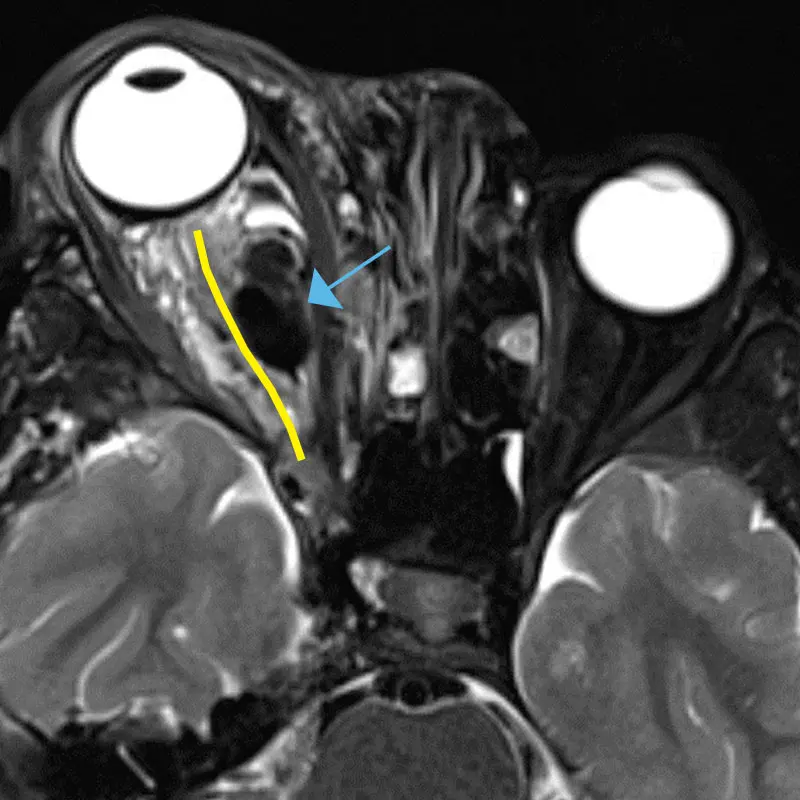

Axial MRI showing optic nerve course (yellow line) with compression by AVM (blue arrow)

The young patient, Bryson Hadden, faced a welter of issues. From birth, he developed AVMs and venolymphatic malformations in various regions of the head. When his right eye began bulging in August 2021—a condition his mother, Brittny Hadden, recalls as “really nasty-looking and painful”—an MRI and magnetic resonance angiography revealed an intra-orbital arteriovenous as well as multiple intracranial arteriovenous malformations. This tangle of blood vessels, also known as a fistula, forms abnormal connections between arteries and veins, and the resultant expansion of the previously small, low-flow veins compresses the surrounding tissues. It also runs the risk of rupturing and causing massive bleeding.

It proved to be anything but routine surgery, however. “All of us were very nervous about this case because of all the important blood vessels that were connecting to the ophthalmic artery,” says Dr. Elmalem. “If a clot were to form and travel through the artery, the patient would go blind.” Another challenge was the patient’s age—a rambunctious five-year-old who is also on the autism spectrum. The usual access to the vein through the orbit could have led to difficult-to-manage vision-threatening postoperative bleeding from the child rubbing his face or eyes.